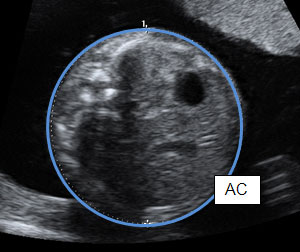

- Обиколка на корема на плода прогнозира и диагностицира по точно феталната ретардация в сравнение с ВРД и дължината на фемура. Следователно серийното изследване на обиколката на корема е метод на избор за откриване на ИУРП.